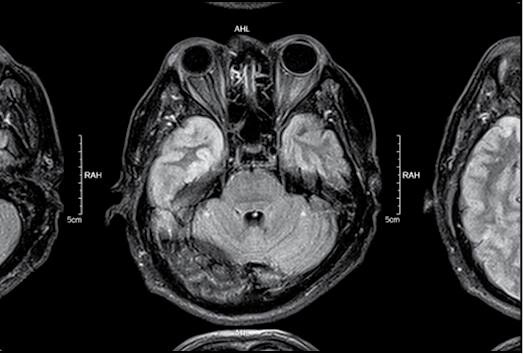

Глядя на природу человека, часто отделяют биологическое (телесное) от психического. Но психика является продуктом деятельности головного мозга. Равно как и все процессы, в том числе болезненные, которые происходят в организме, отражаются на деятельности психики. И существует целый пласт психических расстройств, которые связаны с системными (то есть поражающими все части организма) заболеваниями. Моя врачебная практика началась с отделения сочетанной психической и соматической (телесной) патологии, и именно там связь между телом и духом ощущалась наиболее остро.

«Пациент Б. поступил второй раз и вновь в наше отделение. Прошло полтора месяца, но я узнал имя на титульной странице. Он был одним из семи моих первых пациентов после получения сертификата и поступления на работу. Высокий худощавый старик шестидесяти семи лет. Всю прошлую госпитализацию мы мучились с его давлением. На фоне сахарного диабета, который он дома никогда не контролировал, его давление прыгало то вверх, то вниз, быстро выровнять его не удавалось, из-за чего несколько раз мы переводили пациента в реанимацию, а затем снова возвращали в наше отделение.

Но основной причиной его пребывания тогда в психиатрической больнице была суицидальная попытка. Он подгадал время, когда его дочь и жена, в квартире с которыми он проживал, ушли на рынок. Помылся, поставил иконку на столик, зажег подле нее свечку и лезвием разрезал себе вены. Родные нашли его таким, в крови и в полусознательном состоянии. Так мы с ним и познакомились. Впервые я увидел его худым, ослабленным, с зашитым левым предплечьем. Он всегда вежливо разговаривал со мной, с окружающими, хотя и был несколько ворчливым. О причинах своих действий он отзывался так: «Устал я. В магазин ходить не могу, не работаю, что ж это я за мужик такой. Лежу как бревно целыми днями». Однако это было не все. К тому времени он уже год не ел вместе со своей семьей за одним столом. Требовал, чтобы ему готовили отдельно на его пенсионные деньги. И считал, что шестидесятидевятилетняя жена ему изменяет. Его подозрения усиливались, когда она уходила выбрасывать мусор или на рынок. Он, конечно, не видел, но подозревал в измене у мусорных баков. Мы лечили его почти два месяца, на исходе которых он начал улыбаться, старался помириться с женой и дочерью и хотел жить.

И вот он к нам вернулся с другими симптомами. Теперь из другой больницы, туда его положили из-за гипертонического криза. Он провел там около недели. Но вчера этот немощный старик возбужденно бегал по отделению и даже угрожал медсестрам. Едва дождавшись утра, его перевели в психиатрическую больницу.